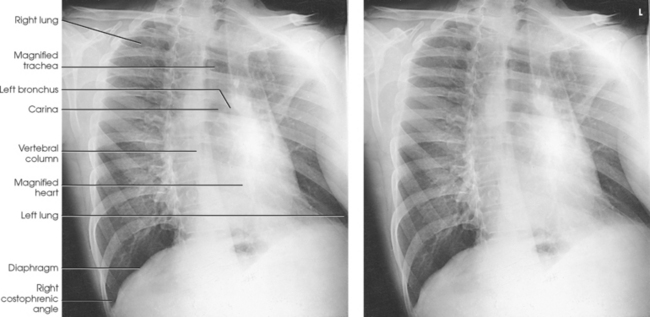

The general shape of the human body, or the body habitus, determines the size, shape, position, and movement of the internal organs. Fig. 10-1 outlines the general shape of the thorax in the four types of body habitus and how each appears on radiographs of the thoracic area.

The thoracic cavity is bounded by the walls of the thorax and extends from the superior thoracic aperture, where structures enter the thorax, to the inferior thoracic aperture. The diaphragm separates the thoracic cavity from the abdominal cavity. The anatomic structures that pass from the thorax to the abdomen go through openings in the diaphragm (Fig. 10-2).

The thoracic cavity contains the lungs and heart; organs of the respiratory, cardiovascular, and lymphatic systems; the inferior portion of the esophagus; and the thymus gland. Within the cavity are three separate chambers: a single pericardial cavity and the right and left pleural cavities. These cavities are lined by shiny, slippery, and delicate serous membranes. The space between the two pleural cavities is called the mediastinum. This area contains all the thoracic structures except the lungs and pleurae.

The lungs are the organs of respiration (Fig. 10-4). They are the mechanism for introducing oxygen into the blood and removing carbon dioxide from the blood. The lungs are composed of a light, spongy, highly elastic substance, the parenchyma, and they are covered by a layer of serous membrane. Each lung presents a rounded apex that reaches above the level of the clavicles into the root of the neck and a broad base that, resting on the obliquely placed diaphragm, reaches lower in back and at the sides than in front. The right lung is about 1 inch (2.5 cm) shorter than the left lung because of the large space occupied by the liver, and it is broader than the left lung because of the position of the heart. The lateral surface of each lung conforms with the shape of the chest wall. The inferior surface of the lung is concave, fitting over the diaphragm, and the lateral margins are thin. During respiration, the lungs move inferiorly for inspiration and superiorly for expiration (Fig. 10-5). During inspiration, the lateral margins descend into the deep recesses of the parietal pleura. In radiology, this recess is called the costophrenic angle (see Fig. 10-5, B). The mediastinal surface is concave with a depression, called the hilum, that accommodates the bronchi, pulmonary blood vessels, lymph vessels, and nerves. The inferior mediastinal surface of the left lung contains a concavity called the cardiac notch. This notch conforms to the shape of the heart.

For radiography of the heart and lungs, the patient is placed in an upright position whenever possible to prevent engorgement of the pulmonary vessels and to allow gravity to depress the diaphragm. Of equal importance, the upright position shows air and fluid levels. In the recumbent position, gravitational force causes the abdominal viscera and diaphragm to move superiorly; it compresses the thoracic viscera, which prevents full expansion of the lungs. Although the difference in diaphragm movement is not great in hyposthenic individuals, it is marked in hypersthenic individuals. Figs. 10-10 and 10-11 illustrate the effect of body position in the same patient. The left lateral chest position (Fig. 10-12) is most commonly employed because it places the heart closer to the IR, resulting in a less magnified heart image. Left and right lateral chest images are compared in Figs. 10-12 and 10-13.